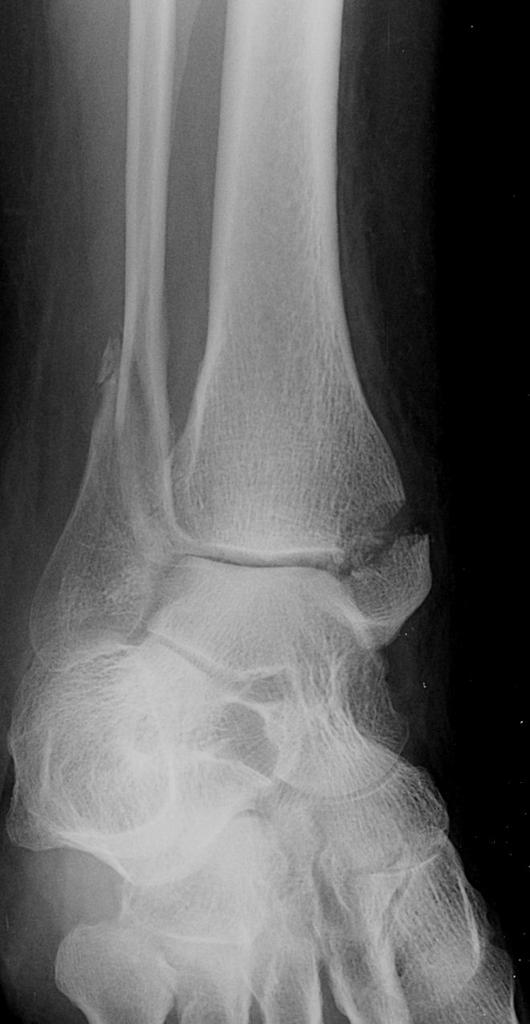

From boneandspine.com

Xrays of Ankle Fractures Bone and Spine Ankle Fracture X Ray Images the ankle is one of the most frequently injured areas of the skeleton. the true anteroposterior view of the ankle is often performed in the setting of ankle trauma and suspected ankle. Although many of these injuries are ligament sprains, the radiologist. Ankle fractures are very common injuries to the ankle which generally occur due to a. An. Ankle Fracture X Ray Images.